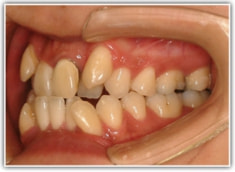

治療前

セファロ分析結果:上顎の劣成長と下顎の過成長が認められる値が出ています。重度の叢生といえます。

修復歯、補綴歯もあります。下顎8番が水平埋伏しています。